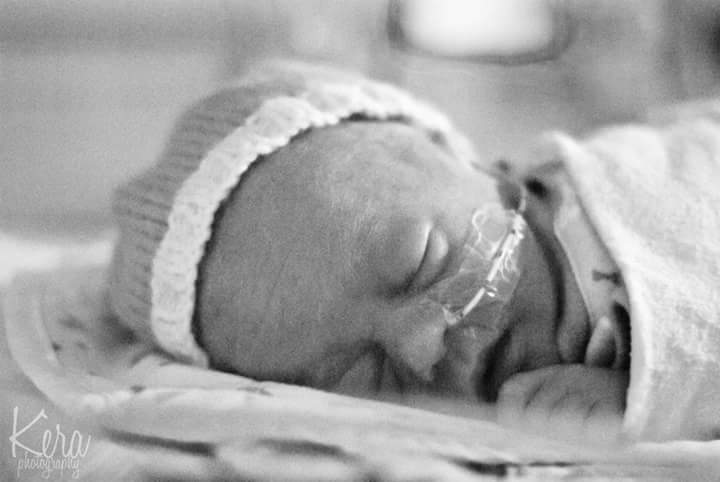

But I still hadn’t seen Aaron.  I got Dylan settled and asked my husband how Aaron is doing.  We found out he was breathing but that he needed to go to the NICU for observation.  The staff finally wrapped Aaron up and brought him to me. At last, I was holding my babies! They let me hold Aaron for only a few seconds and whisked him off to the NICU. Dylan was great. He was 3 pounds 14 ounces and was going to NICU as a feeder and grower.

Given my complicated pregnancy, I had always thought in the back of my mind that my babies would end up in the NICU, but to know your babies are there is a little scary…especially for a first-time mom! The first couple of days I lived in the NICU (since I was still a patient at the hospital myself). I became very acquainted with the friendly and helpful day nurses, but nights were SO hard. I had no clue what it would feel like to leave my babies —now my world —in the hands of strangers. I had no clue what it would feel like to watch and let strangers take care of my babies.  It’s really a gut-wrenching time for parents, especially moms.  It is a motherly instinct to nurture and care for babies and when you are unable to do so, it has devastating effect on your spirit and mind.

On my last day as an admitted patient, I knew I would have to leave my babies.  I felt like making false ailments just so I could stay admitted. Then, my angel walks in! Nurse Kelly Gee! She had the best and most upbeat personality.  She was also a twin mom and a twin grandma, so it felt like she was a nurse made for our family.  I immediately fell in love! She was such a calming and positive support to both my husband and me.  We quickly requested her as our night nurse and our request was granted.  She would be the only one caring for the twins from 7pm to 7am! She was my total ally and ultimate support.

It was Nurse Kelly Gee that I turned to when I didn’t understand the doctor jargon.  She was the understanding shoulder to cry and lean on when I was overwhelmed with emotion. She was the one to help hug, embrace and hold our babies, even while my husband and I were ordered to get some rest. She was the one that told me I had to go on one last date with my husband before the boys came home and she is the one that made my NICU experience less scary.  She was literally our lifesaver during one of the toughest times in our lives.”

“To all the NICU nurses and my beloved Nurse Kelly Gee, you will never know the amount of gratitude and love myself and my whole family have for you! Seeing your baby hooked up to machines and incubators really is overwhelming and can be terrifying for parents.  This special group of nurses, through their compassion and kindness, really eases your mind and makes you truly believe everything will turn out great! Thank you, from the bottom of my heart…thank you for doing what you do, and caring and loving on my babies and all babies in need!”